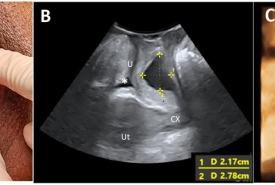

FIGURE 1: (A) A left periurethral mass extending from the left periurethral space to suburethral region measuring 3 cm x 5 cm; (B) Midsagittal view of the pelvic floor showing a cystic mass (*) dorsal to the urethra (U) measuring 2.17 cm x 2.78 cm on translabial perineal ultrasound (TPUS); (C) TPUS view demonstrating a periurethral mass dorsal to the urethra measuring 4.22 cm (width) x 1.99 cm (vertical dimension). (SP: Symphysis pubis; Ut: Uterus; CX: Cervix)